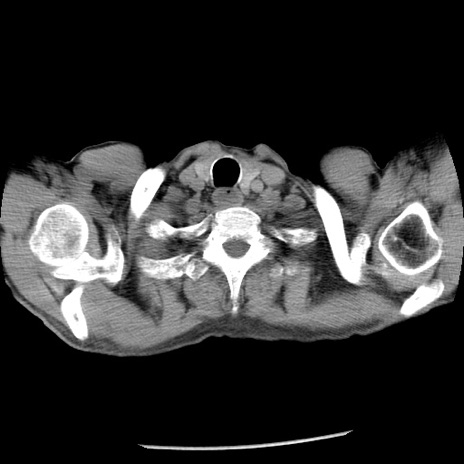

症例26(横断像)

【症例】80歳代男性

【主訴】嘔吐

【現病歴】昨晩2回嘔吐あり、今朝になっても嘔吐あり。来院。

【既往歴】胃潰瘍

【身体所見】意識清明、BT 37.6℃、BP 166/95mmHg、HR 100bpm、SpO2 97%、腹部:平坦・軟、腸蠕動音聴取良好、圧痛なし。

【データ】WBC 21900、CRP 1.46